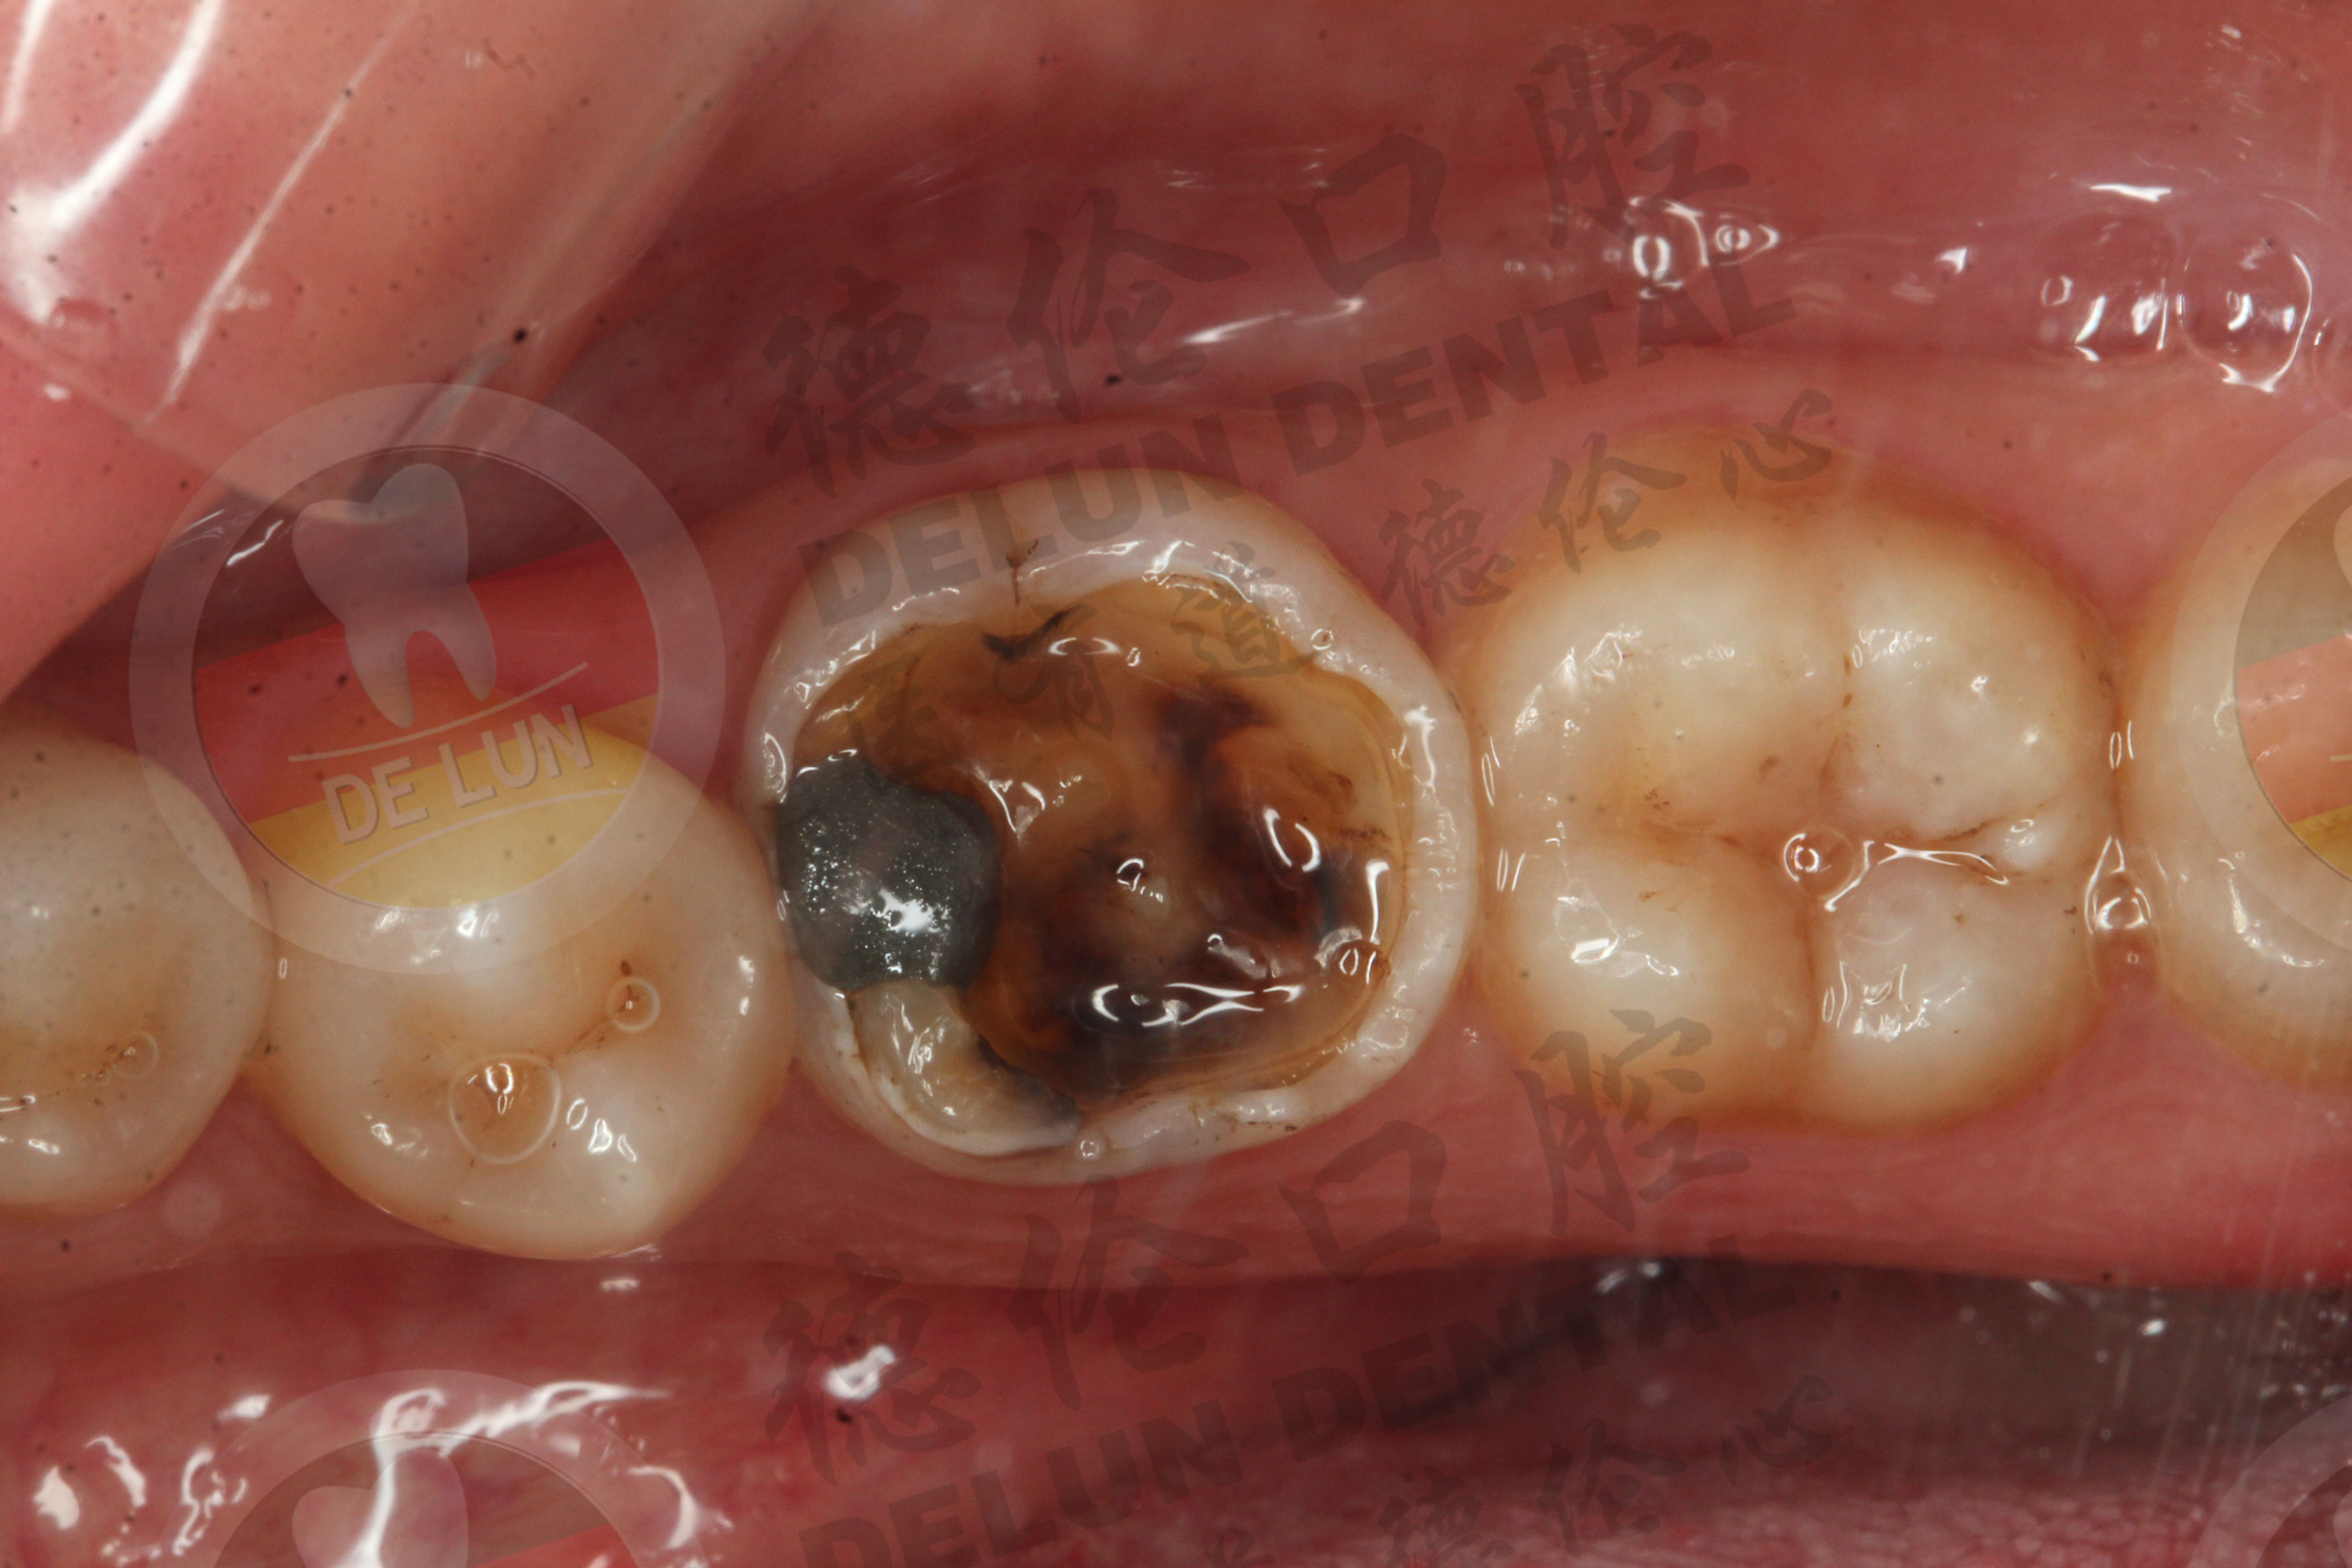

2.龋齿

如果得了龋病,又在刷牙、喝热水、咀嚼食物时出现酸软感,那么就意味着龋齿已经发展到中等深度,到了龋齿发展到深部靠近牙髓时,敏感症状才会很明显,甚至在冷热刺激下出现疼痛感。

1.树脂补牙

如果出现龋齿、楔状缺损、磨耗等疾病导致牙齿敏感,医生会使用复合树脂将牙齿的缺损补起来,从而隔绝外界刺激,缓解牙敏感症状。个别患者出现明显症状,牙髓受到不可逆损伤时,可考虑根管治疗。